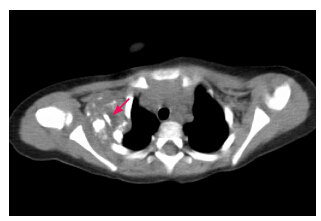

患儿男,1岁,因发现右肩部肿物1周就诊。1周前发现右肩肿物,约小核桃大小,无外伤史。体查:右肩中部皮下可触及肿物,约2cm×2cm大小,不随体位移动,边界清晰,质韧,无血管杂音,无明显压痛。彩超检查示右肩部不均质团块。胸部X线片检查示(图 1):右肩胛骨区见混杂高密度影,内见条片状高密度影,边界不清,临近肋骨未见破坏,性质待查。CT扫描示(图 2):右侧肩胛骨前内侧锁骨后内侧一软组织肿块影,内见多发云絮状、斑片状钙化灶;大小约3.0cm×3.7cm×5.0cm;与邻近肋骨、肩胛骨分界不清,但无明确骨质破坏。入院诊断:软组织软骨瘤;畸胎瘤。家族无类似疾病史。入院后行右侧肩部肿物切除术,术中见肿块位于右肩部锁骨肩胛窝偏下,约5.0cm×3.0cm大小,分叶状,形态不规则,质地硬,来源不明确,颈部未发现肿大淋巴结。术中诊断:右肩部肿块,性质待查。予以右侧肩部肿块完全切除,并送病理学检查,其结果见图 3。术后病理学诊断:钙化性腱膜纤维瘤(右肩)。随访6个月无复发。

图 2 胸部 CT 扫描 可见右侧腋部软组织肿块,内见云絮状、斑片状钙化灶(箭头所示)。